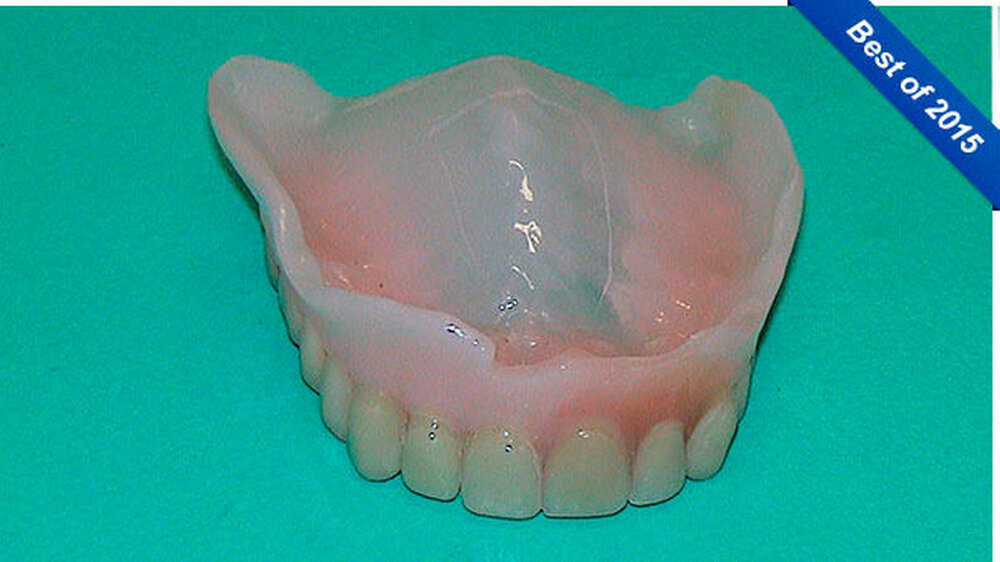

Er schreibt: "Als eine Patientin unsere Praxis aufsuchte, um sich im Notdienst ihre frakturierte totale Oberkieferprothese reparieren zu lassen, so war dies an sich noch kein spektakuläres Ereignis (Abbildung 1). Doch als sie gebeten wurde, auch ihre subtotale Unterkieferprothese mit Drahtklammerfixierung am teil-retinierten Zahn 47 zum Zwecke einer eingehenden Inspektion der Mundhöhle zu entfernen, reagierte sie merkwürdig zögerlich, unwillig und peinlich berührt. Erst nach eindringlicher Bitte gab sie nach und entfernte den Zahnersatz (Abbildung 2).